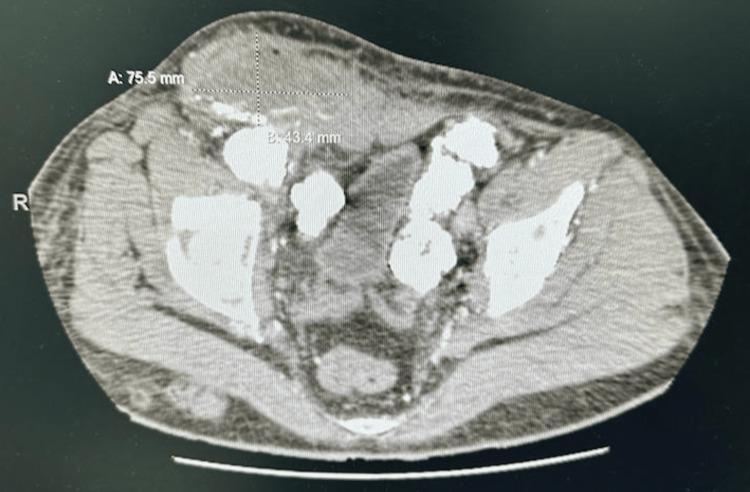

Mönckeberg's disease, a rare medial calcific arteriosclerosis, predominantly affects lower extremity arteries with an unclear etiology. If untreated, severe complications like ischemic necrosis and gangrene may arise. We present a case of a 28-year-old male with spontaneous lower limb swelling, abscess, and itching. Despite a history of deep vein thrombosis and warfarin therapy, Mönckeberg's disease was suspected. Imaging revealed diffuse vascular calcification of the media of the arterial wall bilaterally in the right and left femoral vessels with heterogenous irregular soft tissue collection in the right with suspected infection. Following treatment, the patient's symptoms improved, and follow-up imaging showed resolution of fluid collections and improved calcification appearance. This report highlights the importance of considering Mönckeberg's disease in the differential diagnosis of lower extremity swelling and the need for timely management to prevent serious complications.

门克贝格氏病是一种罕见的中层钙化性动脉硬化,主要累及下肢动脉,病因不明。若不治疗,可能会出现缺血性坏死和坏疽等严重并发症。我们报告一例28岁男性病例,该患者出现自发性下肢肿胀、脓肿和瘙痒。尽管有深静脉血栓形成病史且接受了华法林治疗,但仍怀疑患有门克贝格氏病。影像学检查显示双侧股血管动脉壁中层弥漫性血管钙化,右侧有不均匀不规则软组织聚集,怀疑有感染。经过治疗,患者症状改善,随访影像学检查显示积液消失,钙化表现改善。本报告强调了在下肢肿胀的鉴别诊断中考虑门克贝格氏病的重要性,以及及时治疗以预防严重并发症的必要性。